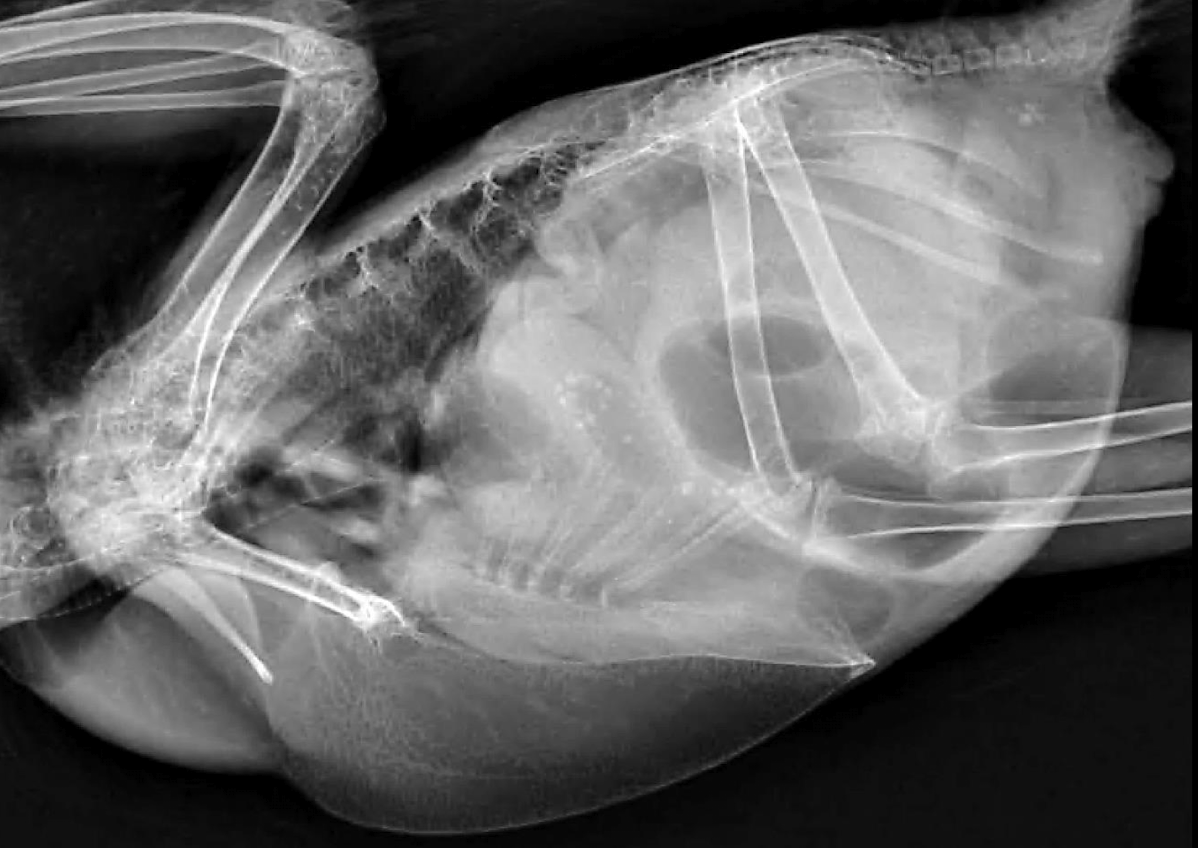

Correct radiograph positioning VD

Correct radiograph positioning Lateral

Normal avian body xray

Normal avian lateral xray